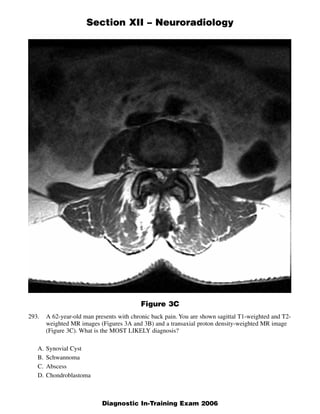

The document discusses several radiology cases involving the brain and spine. Question 291 presents CT scans of a woman with headaches and asks for the most likely diagnosis of a fat-containing extraconal orbital mass. Question 292 shows MR images of a woman with extremity weakness and asks for the most likely diagnosis of multiple brain and spine lesions. Question 293 presents MR images of a man with back pain and asks for the diagnosis of a posterior spinal mass seen on the images.